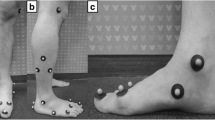

All participants were required to visit the test laboratory for a single testing session. Before data collection, the participant was clothed in close fitting pants, and then subjected to 5 min of low intensity jogging as a warm-up. Subsequently, they were required to walk barefoot at a self-selected speed on a 5-m walkway. The tested foot was randomly selected from asymptomatic and bilaterally symptomatic participants. Painful feet were selected in participants with unilateral symptoms. A Vicon motion capture system (100 Hz; Vicon Motion Systems Ltd., Oxford, UK) with eight cameras was used to assess the three-dimensional motion of the foot. Reflective markers (9 mm in diameter) were attached to the skin, according to the marker set of the Leardini foot model (Fig. 1) [18]. This multisegmental foot model included the shank, calcaneus, midfoot, and metatarsus. A force plate (1000 Hz, AMTI, Watertown, MA, USA) was used to capture the ground reaction forces and identify the stance phase of the gait. Motion and force data were collected synchronously using Vicon Nexus software. Three successful trials with heel contact to the ipsilateral toe-off were performed on the force plate (the entire stance phase of the foot) [12]. Walking speed was recorded using a digital camera (60 Hz) [19].